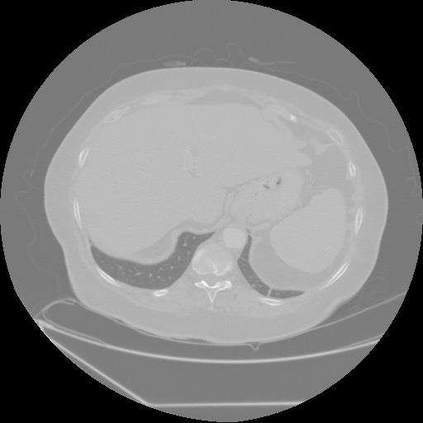

Sparse-view computed tomography (CT) is known as a widely used approach to reduce radiation dose while accelerating imaging through lowered projection views and correlated calculations. However, its severe imaging noise and streaking artifacts turn out to be a major issue in the low dose protocol. In this paper, we propose a dual-domain deep learning-based method that breaks through the limitations of currently prevailing algorithms that merely process single image slices. Since the scanned object usually contains a high degree of spatial continuity, the obtained consecutive imaging slices embody rich information that is largely unexplored. Therefore, we establish a cascade model named LS-AAE which aims to tackle the above problem. In addition, in order to adapt to the social trend of lightweight medical care, our model adopts the inverted residual with linear bottleneck in the module design to make it mobile and lightweight (reduce model parameters to one-eighth of its original) without sacrificing its performance. In our experiments, sparse sampling is conducted at intervals of 4{\deg}, 8{\deg} and 16{\deg}, which appears to be a challenging sparsity that few scholars have attempted before. Nevertheless, our method still exhibits its robustness and achieves the state-of-the-art performance by reaching the PSNR of 40.305 and the SSIM of 0.948, while ensuring high model mobility. Particularly, it still exceeds other current methods when the sampling rate is one-fourth of them, thereby demonstrating its remarkable superiority.